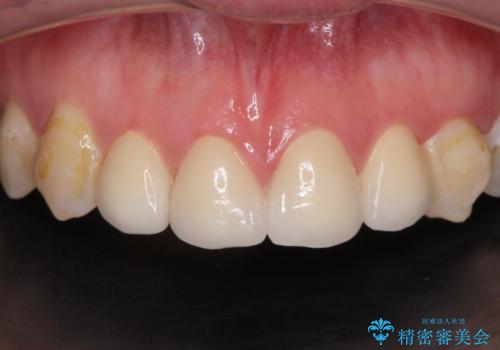

変色してきた歯とプラスチックのクラウン オールセラミッククラウン治療